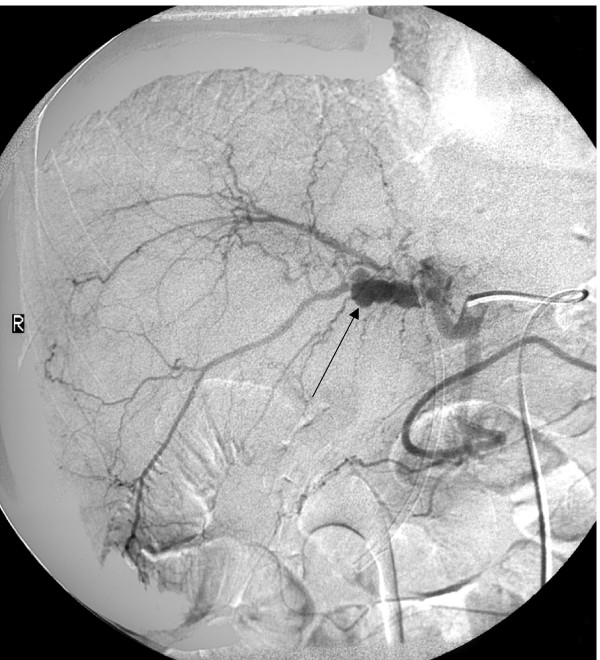

胆囊管综合征者开腹手术中常可见到胆囊增大,并有一定程度扩张,手指按压胆囊后胆汁不能排空。其胆囊本身可无异常,胆囊管组织病理检查常常见到轻度到中度的炎性改变,管壁增厚或有较典型的增生性改变。